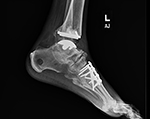

Our standing xray protocol is used to determine the overall shape, structure and integrity of the ankle and foot, while facilitating a comparison with the opposite side. The x-rays also assist in the evaluation of associated conditions.

If you are a candidate for an ankle replacement, we will then obtain a CT (computed tomography) scan with multiple views creating a 3D assessment of your unique anatomy.

The CT scan allows us to create the patient-specific parameters used to plan and perform your surgical procedure with enhanced accuracy.